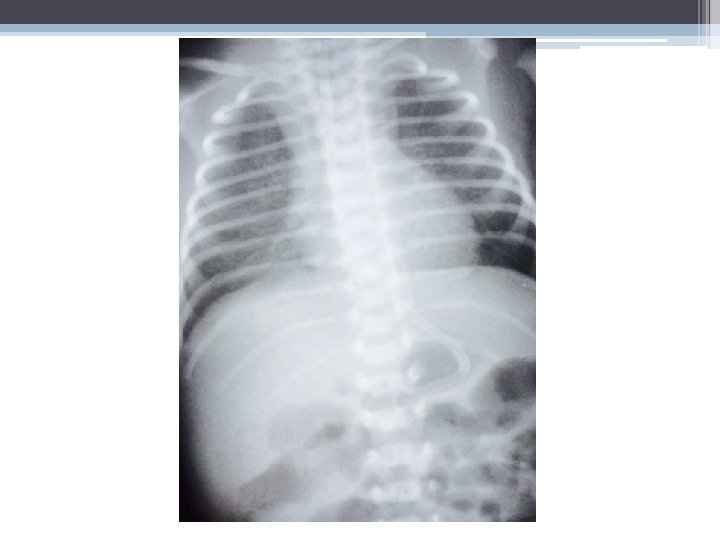

• Rx de tórax: com 4 horas de vida

RADIOGRAFIA • Padrão reticulogranular (“vidro moído”): microatelectasias + edema intersticial • Broncograma aéreo (lobo superior) • RX inicial normal. Evolução para padrão típico em 6 -12 h

Nosso paciente: